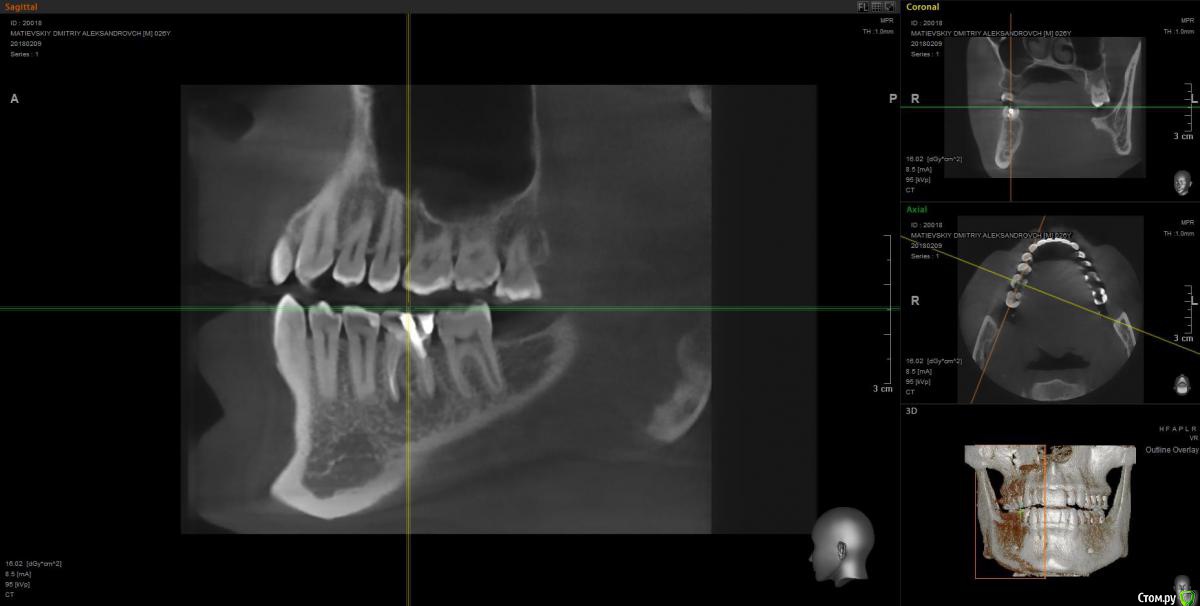

Dmitry91 Опубликовано 13 февраля, 2018 Поделиться Опубликовано 13 февраля, 2018 Добрый день, уважаемые доктора и знатоки! Прошу вашей помощи или мнения по ситуации. Есть проблемный 6й зуб на правой нижней челюсти с огромной пломбой на штифте.Внизу у корней круглые образования (кисты). Под пломбой, похоже, кариес. Стоит ли удалять зуби ставить имплант? Или есть возможность сохранить зуб? Что посоветуете? Если имплант, то какой лучше? Второй вопрос. Нужно ли удалять верхние зубы мудрости (нижних нет)? Похоже рядом с ними на 7ках естьконтактный кариес из-за того, что между зубами мудрости и 7ками застревает пища. Приложил скрины КТ и само 3D КТ в архиве, ссылка ниже. https://yadi.sk/d/kfX43ds43SMxCo Если нужно посмотреть фото с другой стороны, могу сделать. Кто поможет, заранее спасибо!) Ссылка на комментарий

Irouil Опубликовано 13 февраля, 2018 Поделиться Опубликовано 13 февраля, 2018 Удалять восьмерку (вижу только одну) - ОБЯЗАТЕЛЬНО! Удалять шестёрку? Я перспективы лечения не вижу. Какой имплант ставить? Самый надёжный, без оглядки на эстетику. Ссылка на комментарий

DmitrySH Опубликовано 13 февраля, 2018 Поделиться Опубликовано 13 февраля, 2018 ? Или есть возможность сохранить зуб? Если хотите гарантий, то удаляйтеЕсли есть желание сохранить зуб, то можно перелечить. Очаги воспаления скорее всего пройдут, но зуб будет достаточно хрупкий и ненадежный. Соответственно без гарантии. А по стоимости примерно равносильно имплантации Ссылка на комментарий

колесников Опубликовано 14 февраля, 2018 Поделиться Опубликовано 14 февраля, 2018 6ка удаляется. Желательно одномоментно поставить Имплант. Рекомендую Astra tech. Из дополнительных манипуляций будут:формирователь,0,5г костного материала, пластика десны. Верхняя восьмерка ,с этой стороны , так же удаляется. Ссылка на комментарий